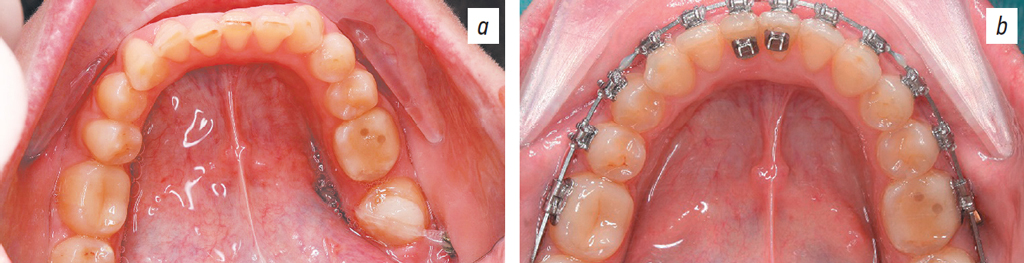

Empower braces (CuNiTi 0.14; American Orthodontics, USA) were installed on the maxilla (Figs. 10, 11).

Fig. 11. Occlusal projection: the upper (a) and the lower (b) dental arches.

Рис. 11. Окклюзионная проекция верхнего (a) и нижнего (b) зубных рядов.

One month after braces were installed on the maxilla, nano-osteoperforation of the roots of teeth 7, 6, 9, 10, and 11 (ISO designations 12, 13, 21, 22, and 23, respectively) was performed, and a BioEdge 16×16 archwire was installed (Fig. 12).

After installing braces on the mandible, nano-osteoperforation in FDI quadrants 3 and 4 was performed. Figs. 13 and 14 show the effect of nano-osteoperforation after 4 weeks of orthodontic treatment.

Fig. 13. Occlusal projection of the upper dental arch before (a) and after (b) nano-osteoperforations.

Рис. 13. Окклюзионная проекция верхнего зубного ряда: до (a) и после (b) нано-остеоперфорации.

Fig. 14. Occlusal projection of the lower dental arch before (a) and after (b) nano-osteoperforations.

Рис. 14. Окклюзионная проекция нижнего зубного ряда до (a) и после (b) нано-остеоперфорации.